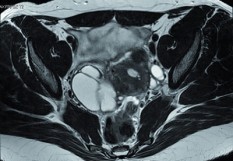

L’urologue est au premier chef concerné par l’endométriose, depuis le dépistage quand les premiers signes sont urologiques, et jusqu’à la gestion des séquelles urinaires éventuelles des traitements. Plus de 10 % des femmes en âge de procréer ont effectivement une endométriose, caractérisée par la présence de tissu endométrial (cellules glandulaires et stromales) en dehors de l’utérus, dans la cavité abdominale. Si elle est parfois une découverte de hasard à l’occasion d’un bilan d’infertilité, elle est le plus souvent symptomatique, associant à des degrés divers selon les organes touchés (colon, rectum, muscles, vagin, urètre, vessie, etc.) douleurs pelviennes, saignements, troubles sexuels, digestifs… et urinaires. Elle peut être de trois types : superficielle, intéresser l’ovaire uniquement (endométriome) ou infiltrer les tissus en profondeur, l’utérus étant au cœur du pelvis. Par ailleurs, l’intensité des symptômes, y compris urinaires, n’est pas corrélée à la sévérité de l’endométriose. « S’agissant de l’arbre urinaire, relève le Pr Jean-Nicolas Cornu, responsable du Comité d’Urologie et de Pelvipérinéologie de la Femme (CUROPF) à l’AFU, chirurgien urologue au CHU de Rouen, peuvent coexister à des degrés divers des troubles de remplissage (urgences et pollakiuries) et/ou de vidange (ressentie comme capricieuse ou incomplète) de la vessie et des douleurs  liés à une infiltration des tissus accompagnée d’un syndrome irritatif, à des lésions sur les uretères et/ou une inflammation “de continuité“ encore mal comprise, les organes communiquant par des messages neurologiques projetés. L’utérus et la vessie ont des racines nerveuses communes et la souffrance du premier déclencher des messages nociceptifs à destination du cerveau, mais aussi de la seconde via des neurones partagés et perturber son fonctionnement. Une femme sur 2 souffrant d’une endométriose sévère rapporte simultanément des troubles urinaires. Cette même logique d’interactions explique les troubles digestifs, vessie et rectum empruntant les mêmes voies. « Ainsi, au stade du diagnostic, s’il n’a pas été posé auparavant sur des signes évocateurs d’ordre gynécologique, précise le Pr Xavier Gamé, Comité de Neuro-Urologie de l’AFU, chirurgien urologue au CHU Rangueil de Toulouse, une endométriose, que l’on sait être la première cause de douleurs pelviennes chroniques chez la femme, doit être évoquée sur des signes urinaires parfois déroutants ; une IRM pelvienne permet alors d’écarter une atteinte de la vessie ou à l’inverse d’objectiver des nodules. Une cicatrice de la vessie qui pérennise la symptomatologie (des troubles de stockage) pourrait être une explication d’une hyperactivité vésicale, à explorer.